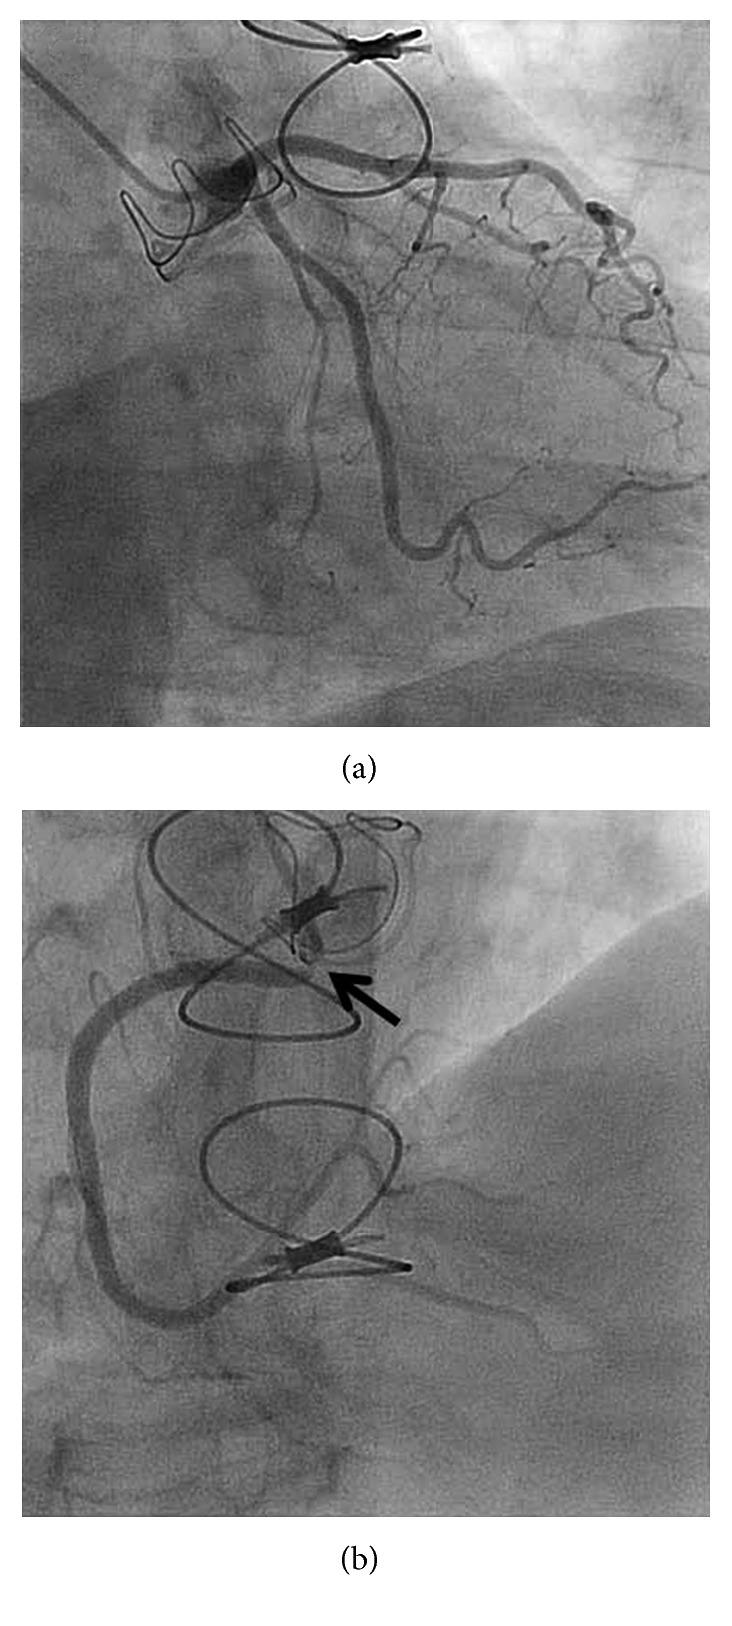

Coronary ostial stenosis is a rare but potentially life-threatening complication that occurs in 1%-5% of patients who undergo surgical aortic valve replacement (SAVR). Symptoms typically appear within the first 6 months and almost always within a year after SAVR. We report an unusually delayed presentation of non-ST segment elevation myocardial infarction due to coronary ostial stenosis 22 months after SAVR. A 71-year-old woman underwent uncomplicated SAVR with a bioprosthetic valve in August 2015 for severe aortic stenosis. A preoperative coronary angiogram demonstrated widely patent left and right coronary arteries. In June 2017, the patient presented to the hospital with chest pain. An electrocardiogram demonstrated 1 mm ST segment depression in the anterolateral leads, and serum troponin I level was elevated to 2.3 ng/ml. Diagnostic coronary angiography revealed severe ostial stenosis (99%) of the right coronary artery. A bare-metal stent was successfully placed with an excellent angiographic result, and the patient was asymptomatic at 4 months of follow-up after the procedure. As seen in our case, coronary ostial stenosis should be considered in the differential diagnosis of chest pain or arrhythmia in patients presenting with a history of SAVR, even if the procedure was performed more than 1 year prior to presentation.

冠状动脉开口狭窄是一种罕见但可能危及生命的并发症,发生在1%-5%接受外科主动脉瓣置换术(SAVR)的患者中。症状通常在术后前6个月内出现,几乎总是在SAVR术后一年内出现。我们报告了一例SAVR术后22个月因冠状动脉开口狭窄导致的非ST段抬高型心肌梗死的异常延迟表现。一名71岁女性于2015年8月因严重主动脉瓣狭窄接受了生物瓣膜置换的SAVR手术,手术过程顺利。术前冠状动脉造影显示左、右冠状动脉广泛通畅。2017年6月,该患者因胸痛入院。心电图显示前侧壁导联ST段压低1mm,血清肌钙蛋白I水平升高至2.3ng/ml。诊断性冠状动脉造影显示右冠状动脉严重开口狭窄(99%)。成功置入裸金属支架,血管造影结果良好,术后4个月随访时患者无症状。正如我们病例中所见,对于有SAVR病史的胸痛或心律失常患者,即使手术在出现症状前1年以上进行,在鉴别诊断时也应考虑冠状动脉开口狭窄。